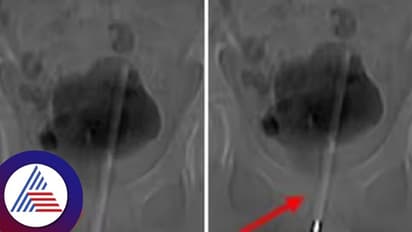

12 ವರ್ಷದ ಬಾಲಕನ ಮೂತ್ರಕೋಶದಿಂದ ವೈದ್ಯರು ಥರ್ಮೋಮೀಟರ್ನ್ನು ತೆಗೆದುಹಾಕಿದ್ದಾರೆ. ಸುದೀರ್ಘ ಶಸ್ತ್ರಚಿಕಿತ್ಸೆಯ ಮೂಲಕ ವೈದ್ಯರು 12 ವರ್ಷದ ಮಗುವಿನ ಮೂತ್ರಕೋಶದಿಂದ ಥರ್ಮೋಮೀಟರ್ನ್ನು ತೆಗೆದುಹಾಕಿದ್ದಾರೆ. ಹಸ್ತಮೈಥುನದ ಸಮಯದಲ್ಲಿ ಥರ್ಮೋಮೀಟರ್ ಶಿಶ್ನವನ್ನು ಪ್ರವೇಶಿಸಿರಬಹುದು ಎಂದು ವೈದ್ಯರು ಹೇಳಿದ್ದಾರೆ. ಒಂಬತ್ತು ಗಂಟೆಗಳ ಕಾಲ ತೀವ್ರ ನೋವಿನಿಂದ ಬಳಲುತ್ತಿದ್ದ ಮಗುವನ್ನು ಆಸ್ಪತ್ರೆಗೆ ದಾಖಲಿಸಲಾಗಿತ್ತು. ಥರ್ಮೋಮೀಟರ್ ಮೂತ್ರನಾಳವನ್ನು ಪ್ರವೇಶಿಸಿ ಮಗುವಿನ ಮೂತ್ರಕೋಶವನ್ನು ಪ್ರವೇಶಿಸಿದೆ ಎಂದು ಎಕ್ಸ್-ರೇಗಳು ಬಹಿರಂಗಪಡಿಸಿದವು. ಕೀ ಹೋಲ್ ಸರ್ಜರಿ ಮೂಲಕ ಮಗುವಿನ ಮೂತ್ರಕೋಶದಿಂದ ಥರ್ಮಾಮೀಟರ್ ಹೊರತೆಗೆಯಲಾಗಿದೆ ಎಂದು ಆಪರೇಷನ್ ನಡೆಸಿದ ವೈದ್ಯರು ತಿಳಿಸಿದ್ದಾರೆ.

ವೈದ್ಯರನ್ನು ಮೂತ್ರವನ್ನು ಸಂಗ್ರಹಿಸಿದ ಮೂತ್ರಕೋಶಕ್ಕೆ ಅಂಗಾಂಶದಲ್ಲಿ ಸಣ್ಣ ಶಸ್ತ್ರಚಿಕಿತ್ಸೆಯ ರಂಧ್ರವನ್ನು ಮಾಡಿದರು ಮತ್ತು ನಂತರ ಥರ್ಮಾಮೀಟರ್ ಅನ್ನು ಸರಿಯಾದ ಕೋನ ಮತ್ತು ಸ್ಥಾನಕ್ಕೆ ಕುಶಲತೆಯಿಂದ ನಿರ್ವಹಿಸಲು ಸಣ್ಣ ಉಪಕರಣಗಳನ್ನು ಸೇರಿಸಿದರು ಮತ್ತು ನಂತರ ಅದನ್ನು ಕೀ-ಹೋಲ್ ಮೂಲಕ ಹೊರತೆಗೆದರು. ಡಾ. ಚಾಂಗ್ಸಿಂಗ್ ಕೆ, 'ಲೈಂಗಿಕ ಶಿಕ್ಷಣದ (Sex Education) ಕೊರತೆ ಮತ್ತು ಕುತೂಹಲದ ಪರಿಣಾಮವಾಗಿ, ಹಸ್ತಮೈಥುನಕ್ಕಾಗಿ ಮಗು ಥರ್ಮಾಮೀಟರ್ ಅನ್ನು ಶಿಶ್ನಕ್ಕೆ ಸೇರಿಸಿತು' ಎಂದು ಹೇಳಿದರು. ಕಳೆದ ಕೆಲವು ವರ್ಷಗಳಿಂದ ಯುಕೆಯಲ್ಲಿ ಈ ಸಮಸ್ಯೆಯಿಂದ ಬಳಲುತ್ತಿರುವ ಪುರುಷರ ಸಂಖ್ಯೆಯಲ್ಲಿ ಹೆಚ್ಚಳವಾಗಿದೆ ಎಂದು ತಜ್ಞರು ವರದಿ ಮಾಡಿದ್ದಾರೆ.